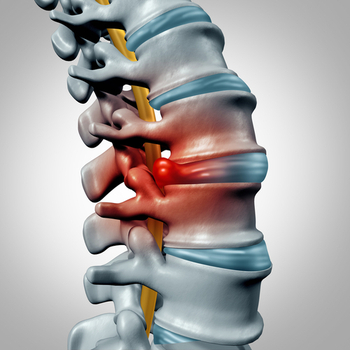

2. 요추 디스크

요추 디스크로 인해 신경근을 압박하게 되면 오금부위로 찌릿찌릿한 통증이 반복됩니다.

디스크로 인한 오금 통증은 좌골신경을 따라 하지로 방사통이 표현되기 때문에 감별 진단할 수 있습니다.

디스크가 나타나는 척추분절의 심부내재근, 극간인대, 후관절 등에 침, 전침, 약침, 봉침의 시술과 함께 전기신경치료를 병행하게 됩니다.